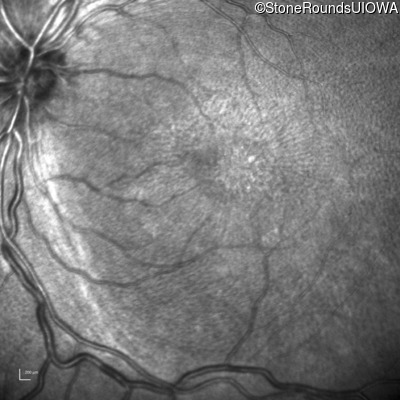

Infrared Fundus Photograph - Right - 20/150

Exemplar